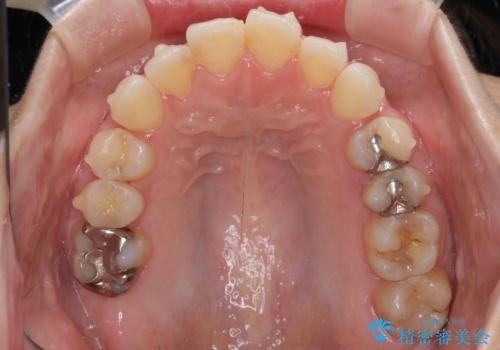

- 前歯のデコボコを気にして来院された患者様です。

主に下顎歯列全体の後方移動とIPR(歯と歯の間を削る)によってデコボコが解消するように設計し、インビザラインにより治療を行うこととしました。

舌突出癖がある方ですと、叢生が解消すると同時に前方に拡大されてしまいますが、ゴムかけをしっかりと行ってくださったこともあり、スッキリとした仕上がりとなりました。